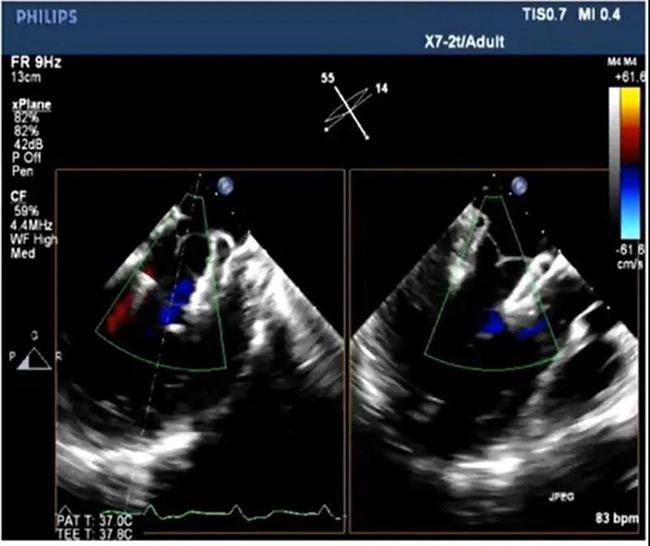

As a leading enterprise in valve industry, especially in the field of mitral valve, Newcastle Medical Co., Ltd. was founded with the mission of "innovation for life", deeply distributed valve field, accurately identified clinical needs, and focused on research and development plan of national 13th five year plan and action plan of scientific and technological innovation of Shanghai Municipal Science and Technology Commission - production, study, research and research Under the framework of "research and development of new type of mitral valve replacement system and achievement transformation" of medical cooperation project, the combination of deep cultivation and medical engineering has successfully developed Mi thos ® Transcatheter mitral valve replacement system (MI thos) ®”)。 Mi-thos ® The system is to transfer the valve to the mitral valve area and expand it after the small incision of the apex, which replaces the lesions of the mitral membrane. Traditional thoracotomy usually takes four to five hours, while Mi thos ® The system can complete valve implantation in just one hour. Mi-thos ® The system is designed according to the pathological anatomy of Chinese people. The innovative design concept of "rigid and flexible" internal and external double-layer stent is adopted to care for the Chinese "heart". Mi-thos ® The D-shaped structure of the outer frame can effectively fit the physiological structure of the mitral valve, and the sealing membrane is used to prevent the leakage around the valve. The unique three-layer barb anchoring structure can effectively prevent valve displacement and improve the safety of operation.